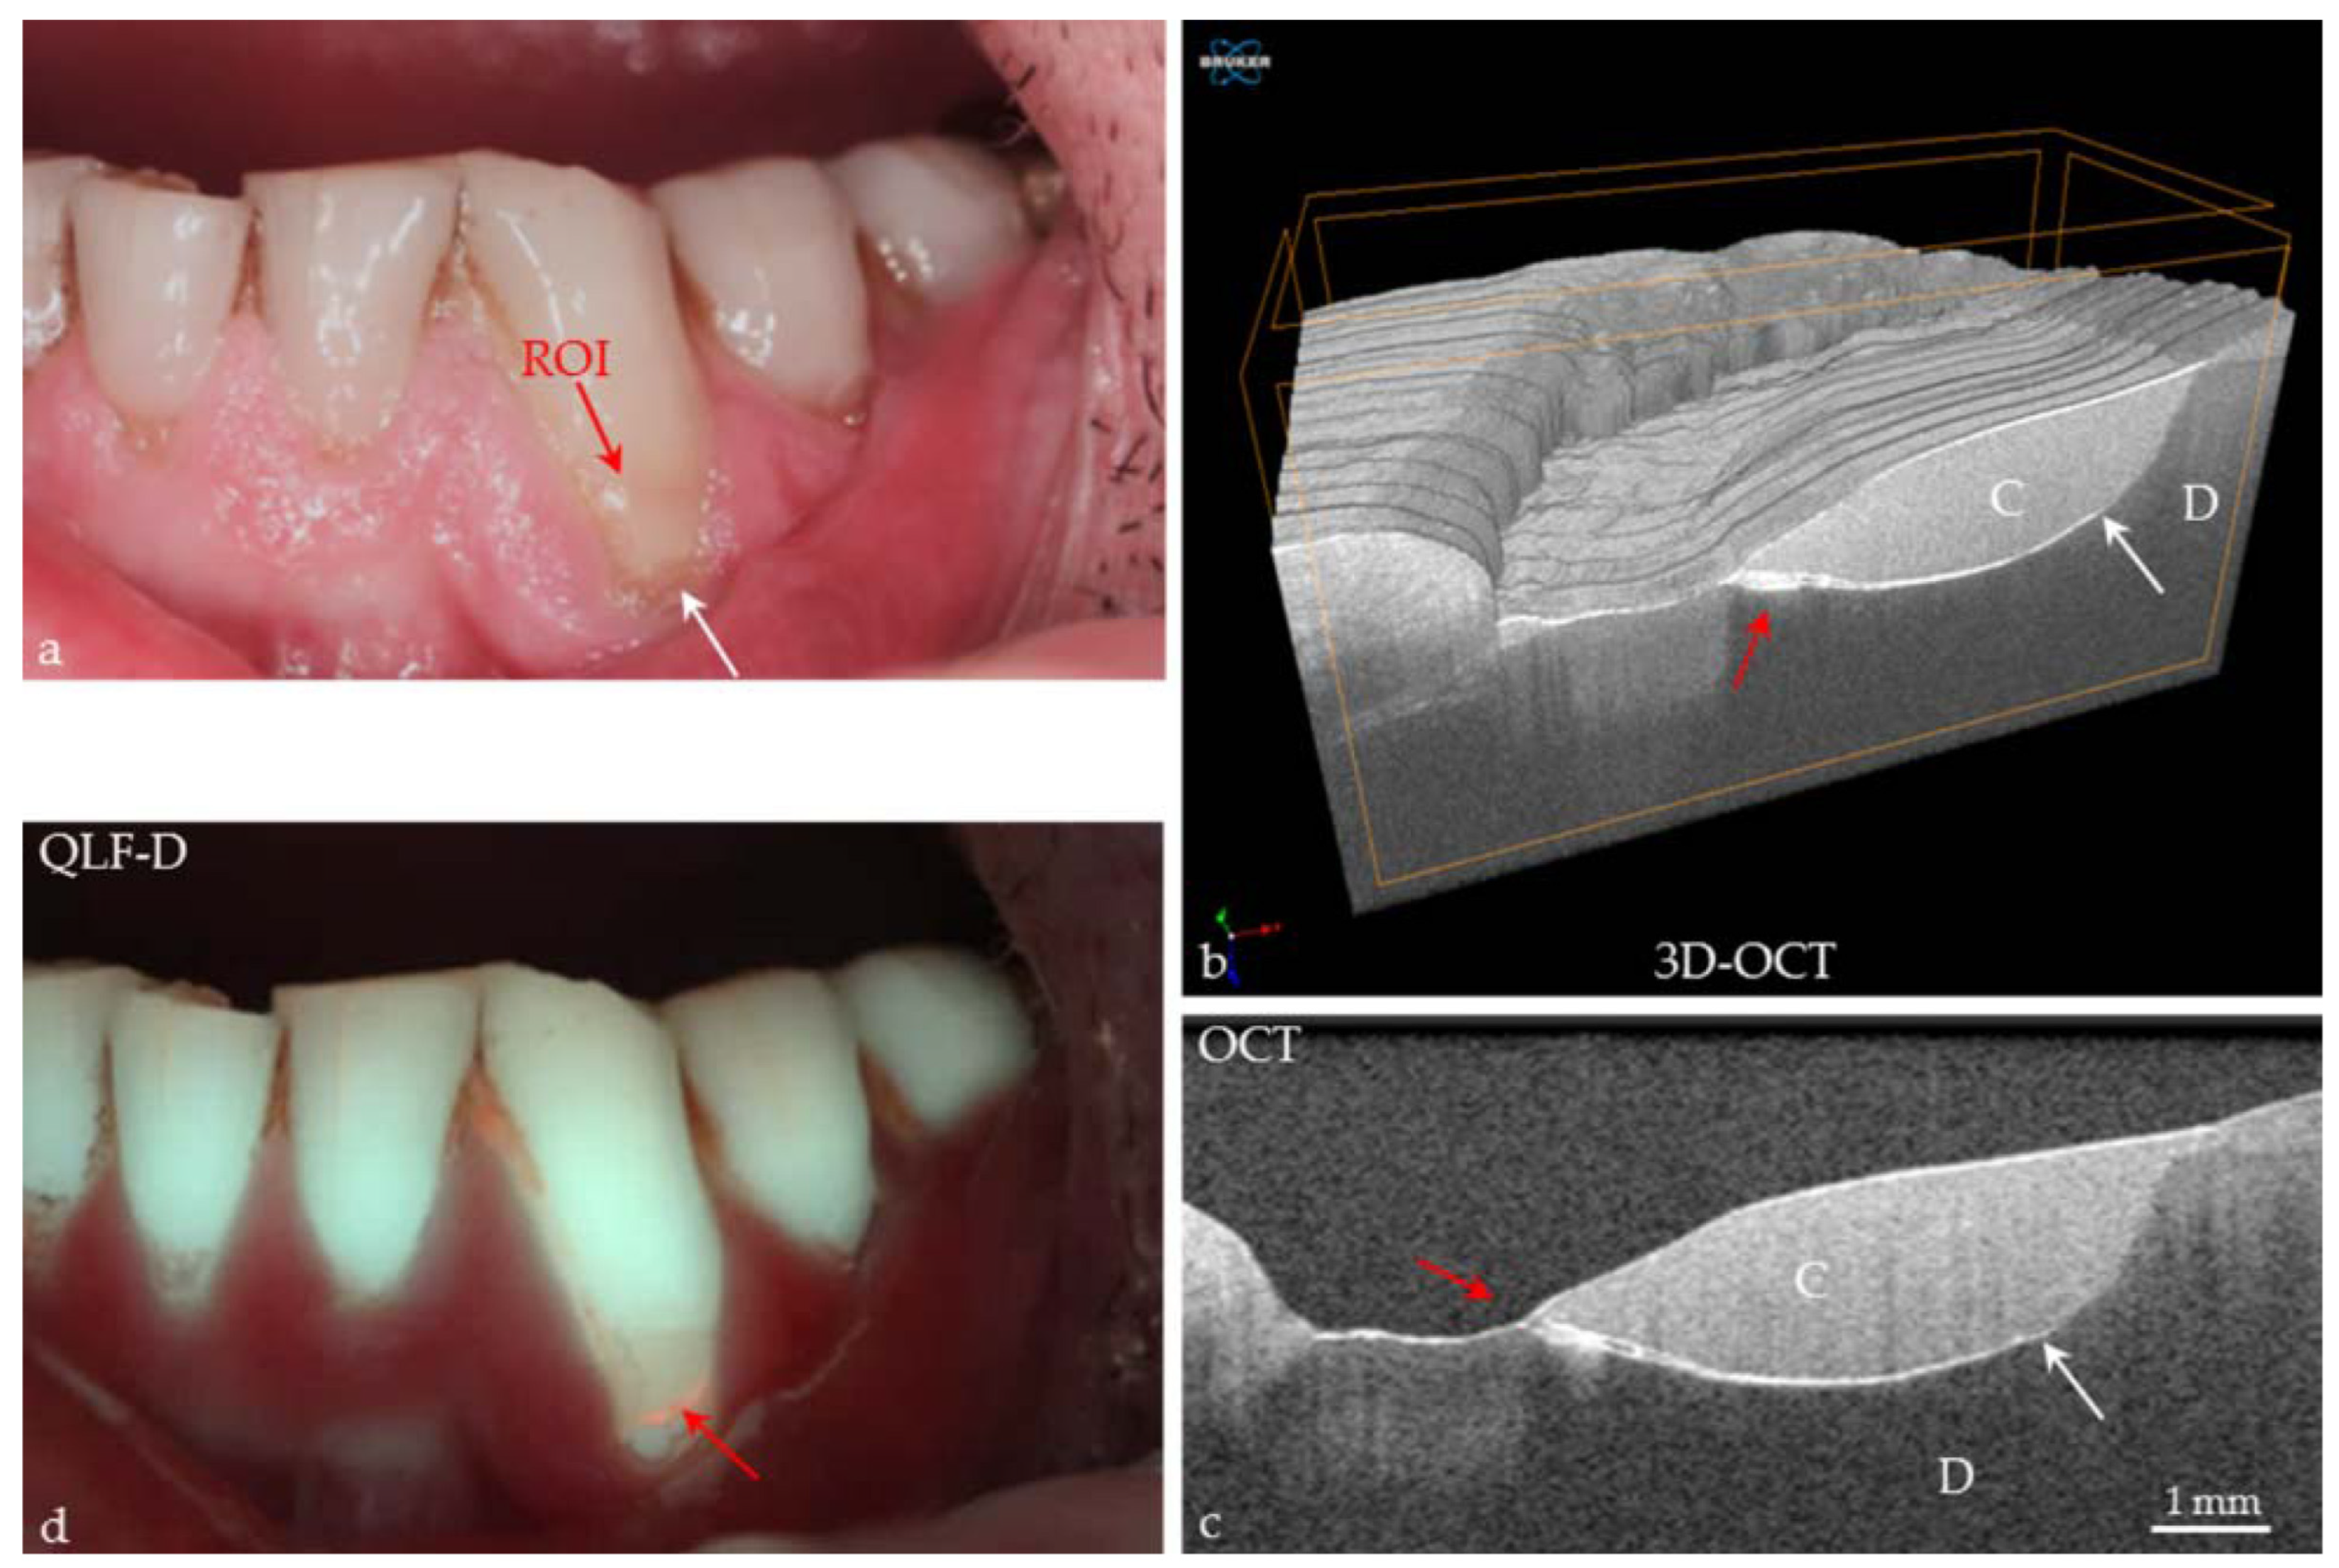

- Le, N.; Cheng, H.; Subhash, H.; Kilpatrick-Liverman, L.; Wang, R.K. Gingivitis Resolution Followed by Optical Coherence Tomography and Fluorescence Imaging: A Case Study. J. Biophotonics 2021, 14, e202100191. [Google Scholar] [CrossRef]